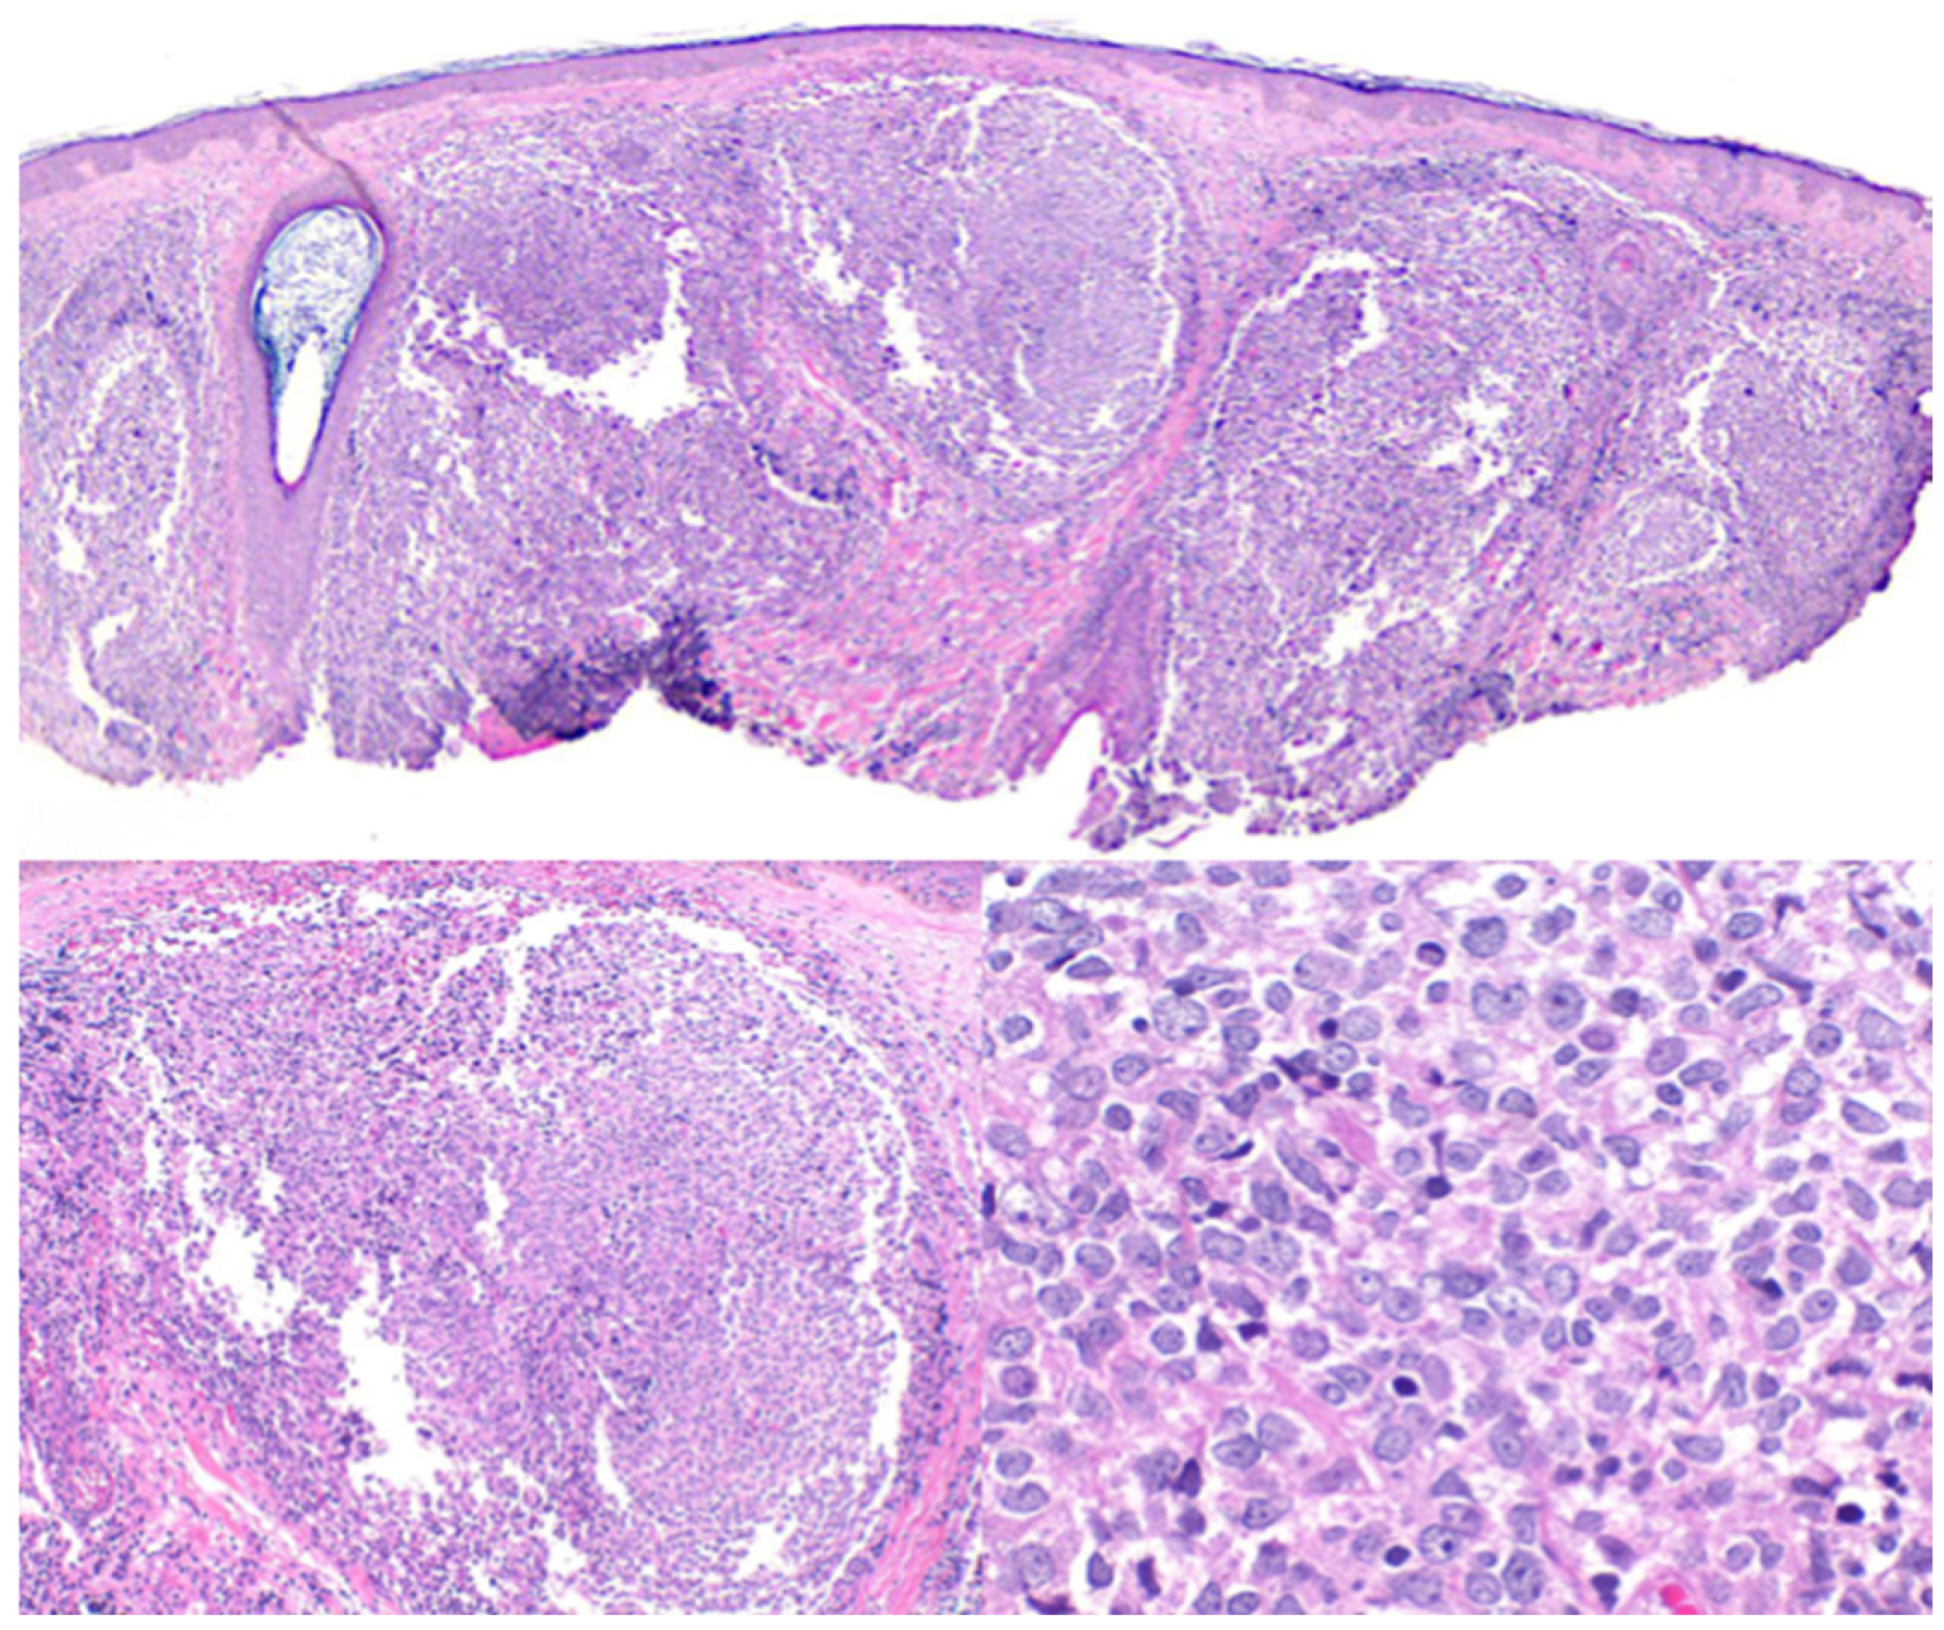

2.1. Primary Cutaneous Follicle Center Lymphoma (PCFCL)

2.2. Primary Cutaneous Marginal Zone Lymphoma/Lymphoproliferative Disorder (PCMZL/LPD)